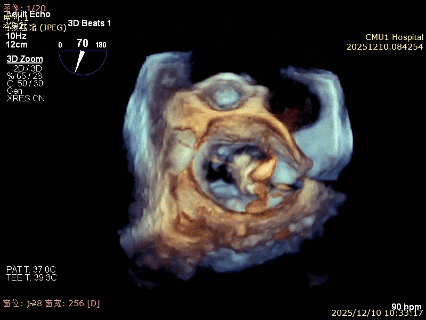

术前3D

术前3Dcolor

3D-TEE二尖瓣相关解剖学参数:后叶长度:22-25mm,前叶长度:31-34mm;瓣环AP径:47mm,ML径:48mm;瓣口面积:约7.8cm²;脱垂宽度:30mm,最大连枷间距:14mm。

术前即刻TEE进一步明确了二尖瓣反流的机制(DMR)及反流程度(5+),重点完善了病变区域二尖瓣解剖结构的评估,预估手术难点/影响手术效果的解剖结构为冗长的二尖瓣后叶(PML约25mm),宽大的脱垂(Flail Width约30mm),超大的连枷间距(Flail gap约14mm)。